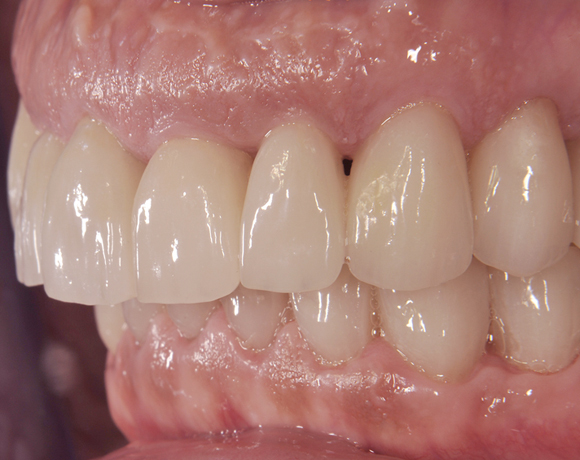

Der vorliegende Patientenfall zeigt eine komplette Neuversorgung der vorhandenen Metallkeramikkronen mit vollkeramischen Restaurationen. Zusätzlich wurde im Oberkiefer die Zahnreihe mit zwei Implantaten, für die fehlenden Molaren, ergänzt. Da keine ausreichende Knochenhöhe vorhanden war wurde ein interner Sinuslift geplant.